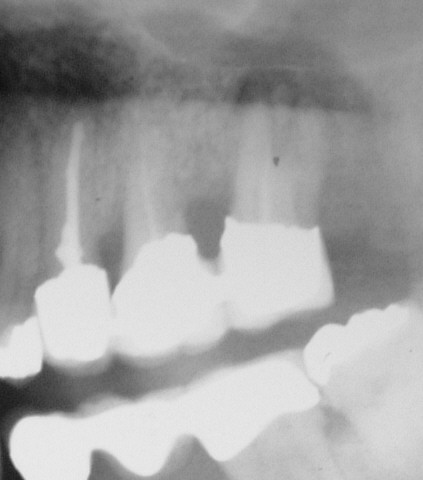

Ausschnitt OPT im Februar 2004 (Klick!)

Dieses OPT wurde anlässlich einer Neuversorgung wegen einer rezidivierend abszedierenden Tasche zwischen 26 und 27 angefertigt. Die Hemisektion solcher relativ kurzen Wurzeln, die stark nach distal gehen, beseitigt ein solches Problem in der Regel zuverlässig. Die Krone an 27 war nach 15 Jahren keineswegs dezementiert, sondern dicht, ging schwer runter, und sowohl der Zement (Havard) als auch Aufbau unter 27 (Ketac-cem) waren völlig trocken. Die Wurzelfüllung war im diagnostizierbaren Bereich unverändert fest. Ein koronales Leck schließen wir daher nach menschlichem Ermessen aus. Der Aufbau wurde nichtsdestotrotz entfernt und nach gründlicher Reinigung der Kavität (Anschleifen, H2O2) in SÄT mit Kunststoff erneuert. Obwohl wir inzwischen mit der Nichtrevison insuffizienter Wurzelfllungen trotz Beschwerdefreiheit schlechte Erfahrungen gemacht und unser Protokoll geändert haben, haben wir uns wegen der mindestens 20-jährigen Beschwerdefreiheit wieder einmal hinreißen lassen.